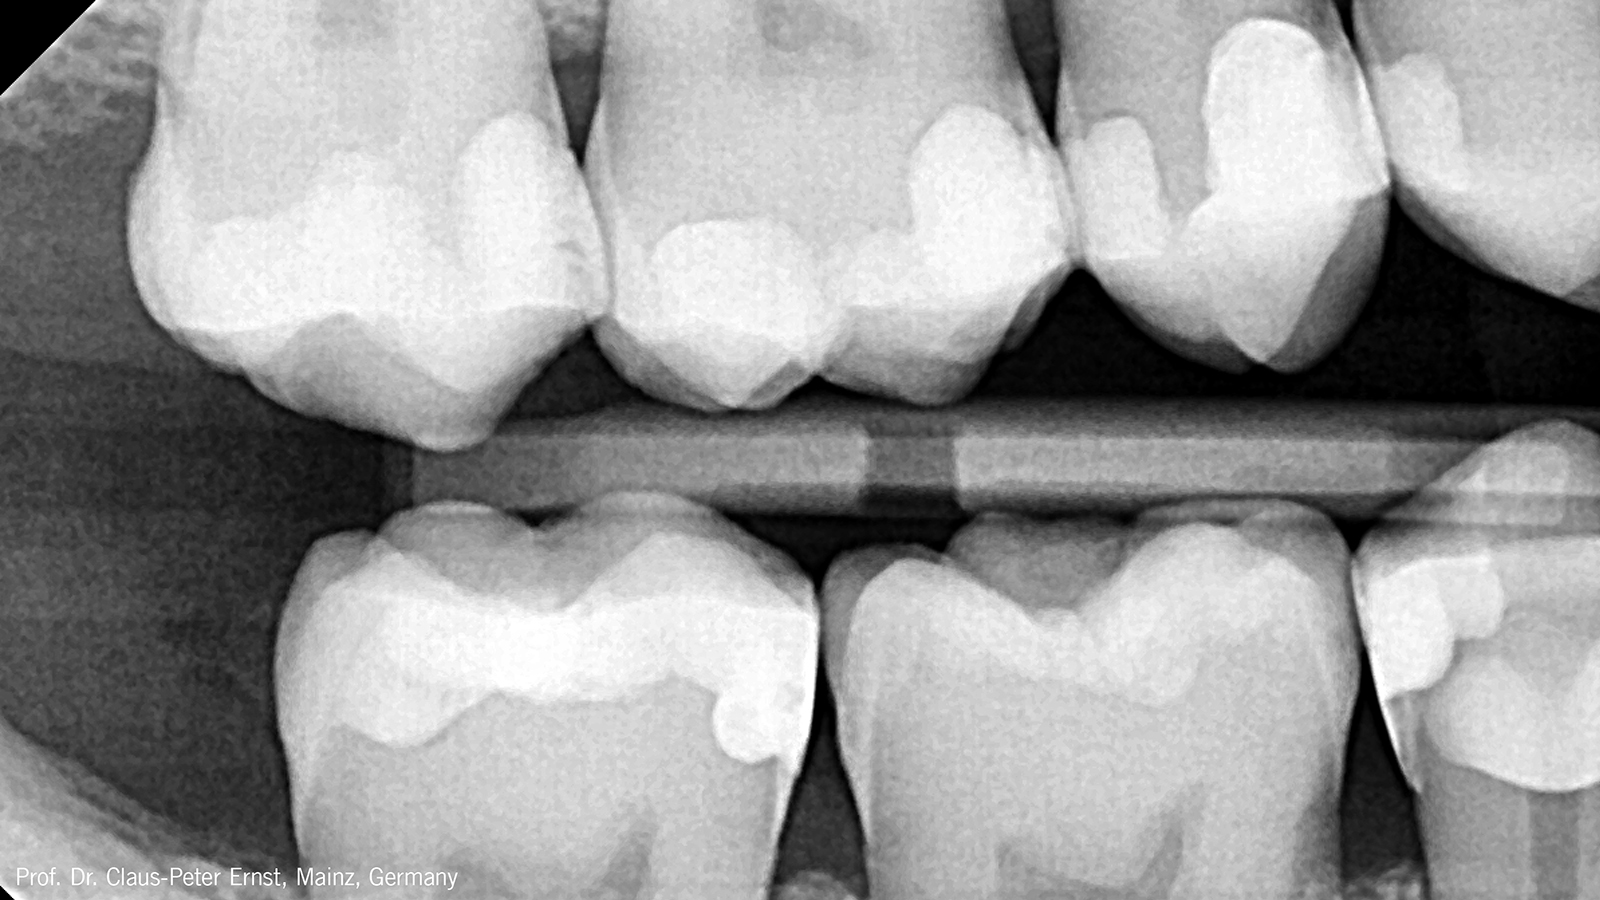

Is Charisma Bulk Flow ONE radiopaque?

Yes, Charisma Bulk Flow ONE fillings are easily recognized on X-rays which supports a reliable diagnosis. Its radiopacity with app. 300%-Al is much higher than the radiopacity of dentine (100%-Al) and enamel (200%-Al).

Its high radiopacity of more than 250%-AL allows for a safe and predictable diagnosis.